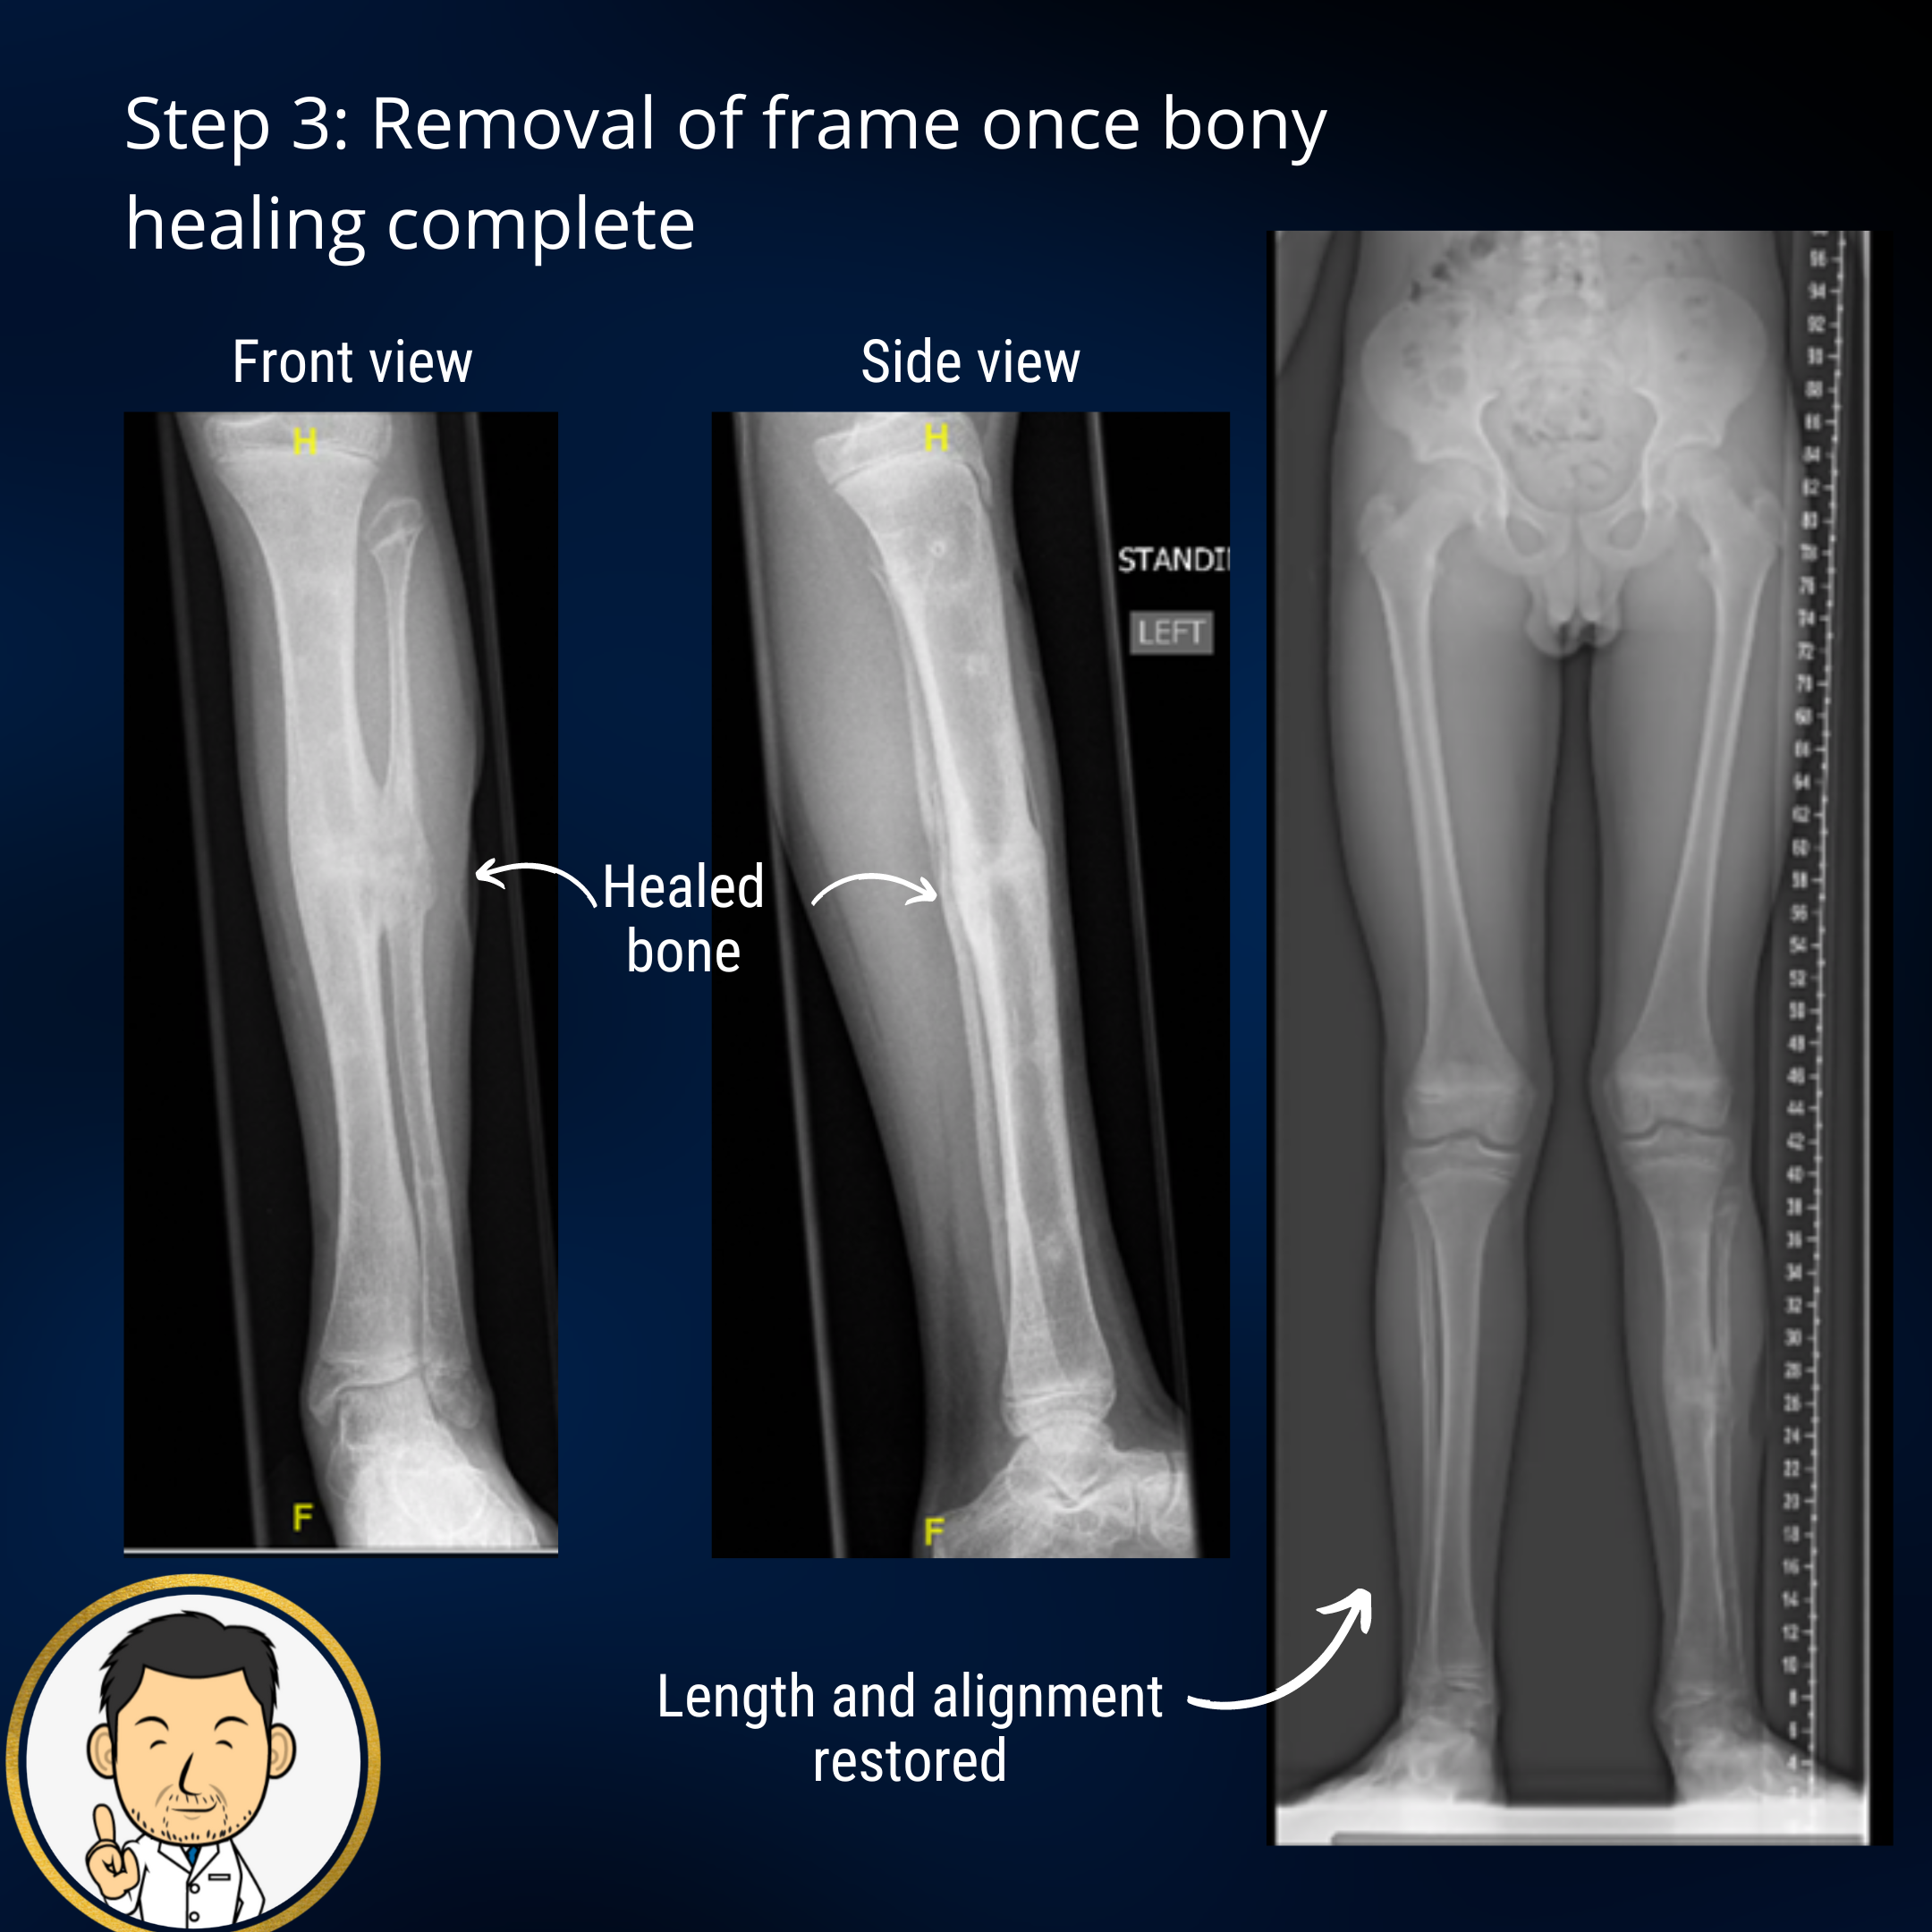

Once the lengthening is complete, the consolidation phase begins. This is where we await the maturation of the new bone in the formed gap to become strong enough to be able to remove the frame. This usually lasts for several months. I am a keen proponent for removing the frame as early as possible. However if the frame is removed too soon, fracture may occur through the bone regenerate......and it's back to square one (well not quite but it does mean more treatment time in a frame or plaster). Strategies I employ to hasten removal of the frame include:

- Cast brace immobilisation after frame removal - If the bone regenerate is almost there, rather than risk fracture leaving the limb free after frame removal I usually apply a cast brace. A cast brace is a plaster cast around the thigh and below the knee connected by adjustable hinges (admittedly does make a patient look a bit like Robocop from the 80s). The plaster cast provides protection and the hinge restriction ensures that deep bending of the knee (which imparts a very large bending moment on the bone) is avoided. Compression of bone regenerate is good, bending is bad. Six weeks in the cast brace is usually sufficient to effect the final stages of bone maturation.